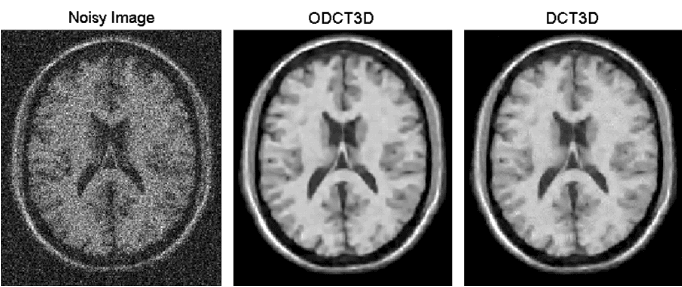

ODCT3D:离散余弦变换是一种与傅里叶变换相关的变换,但是一种实数域的变换,可以用于信号与图像的处理,去噪的主要思路为对图像进行离散余弦变换,设置阈值,滤除高频部分,进行噪声的去除。